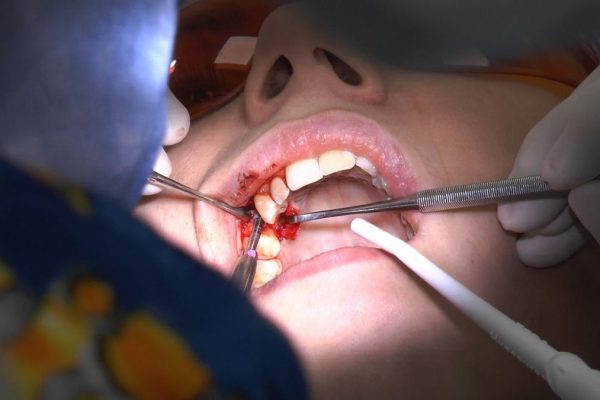

W ostatni weekend czerwca 2018 roku kursanci II Sezonu Preludium Implantologii odbyli piątą, finałową sesję, która w całości podporządkowana była praktyce. W ciągu dwóch dni zabiegowych Lekarze uczestniczący w szkoleniu przeprowadzili szereg zabiegów pod kierunkiem dr n.med. Violetty Szycik. Wszczepili 17 implantów oraz przeprowadzili ekstrakcje i zabiegi regeneracyjne kości. Zabiegi były wykonywane także w sedacji dożylnej z udziałem specjalisty anestezjologii i intensywnej terapii dr Jolanty Grzybowskiej. Preludium implantologii to nowy program edukacyjny dla adeptów implantologii stomatologicznej, którego celem jest wprowadzenie do implantologii poprzez pozyskanie wiedzy w szerokim zakresie i uwzględnieniem szczegółów mających decydujące znaczenie dla powodzenia leczenia implantologicznego. Ale tak jak wszystkie szkolenia w Instytucie Vivadental, w tym wiodące Practiculum Implantologii, zorientowane jest na praktyce i samodzielnym wykonywaniu zabiegów pod kierunkiem Mentora. To najlepsza edukacja w medycynie zabiegowej, a zarazem najlepszy start do implantologii.